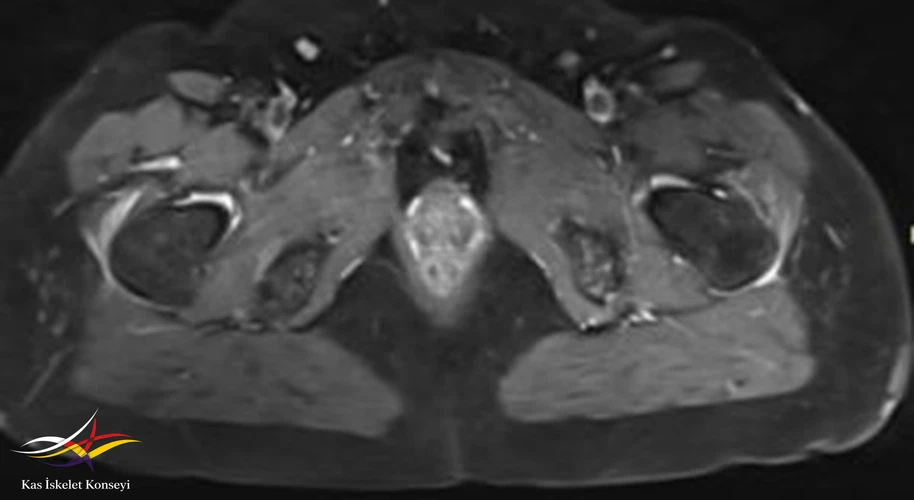

Resim 5. Kalça MRG, aksiyal kesit.

Tedavi için öncelikle trokanterik bursa enjeksiyonları öngörüldü. Bu tedaviden alınacak yanıt görüldükten sonra mevcut lomber patolojisinin (foraminal stenoz) tekrar değerlendirilmesi önerildi. İki yanlı belirgin trokanterik bursit görülmesi nedeniyle polimyalgia romatika açısından da incelenmesi önerildi.